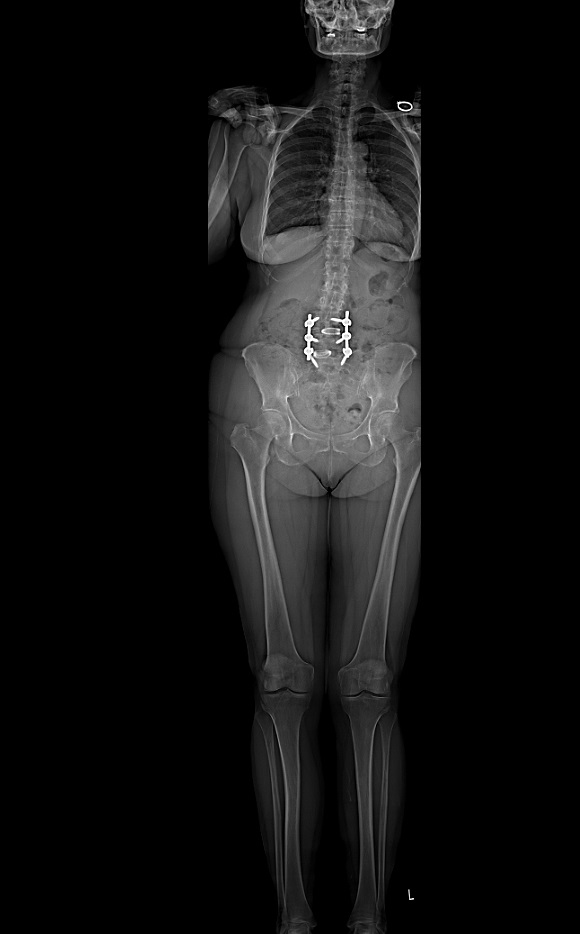

I can’t say enough positive things about Dr. Schwab, his team, and HSS. In December 2017, I had spinal fusion surgery from L-4 to S-1 to correct degenerative scoliosis, spondylolisthesis, and stenosis. I had experienced nerve pain and spasms in my right hip and leg for 22 months. I found my way to Dr. Schwab in November 2017, after seeing numerous specialists and undergoing every conservative treatment such as epidural injections, physical therapy, and even chiropractic.

Meeting Dr. Schwab and Debra Jacobs, nurse practitioner, and his office staff confirmed my impression. They reviewed my images and answered all my questions. I was relieved when Dr. Schwab recommended only one surgery, a two-level posterior fusion (L4 - S1). And, I was happy Dr. Schwab said I would be healed in time for my grandson’s arrival. My last question was, “How quickly can you do it?” Natalia and Dorota quickly and efficiently arranged all of the pre-op testing so I did not need to make another trip to NYC before the surgery. Dr. Schwab also diagnosed a hip bursitis which was adding to my discomfort and recommended an injection. They were able to schedule an appointment in radiology the following day and, of course, he was right - I experienced relief within 24 hours.